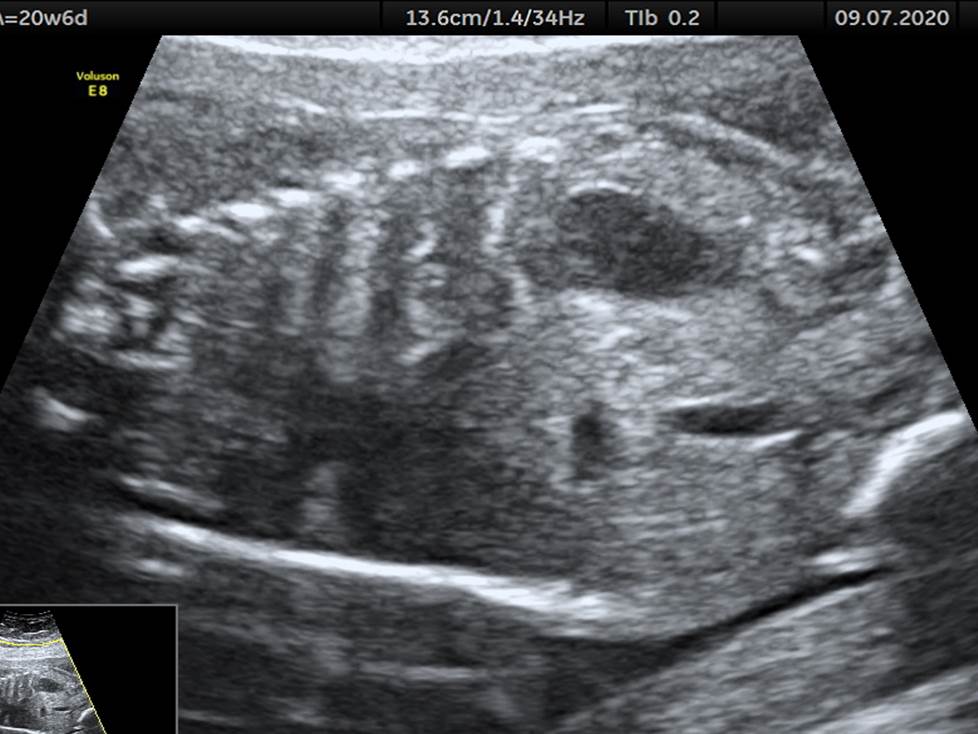

Проанализируйте изображения и видео-клипы плода в 20 недель, установите диагноз